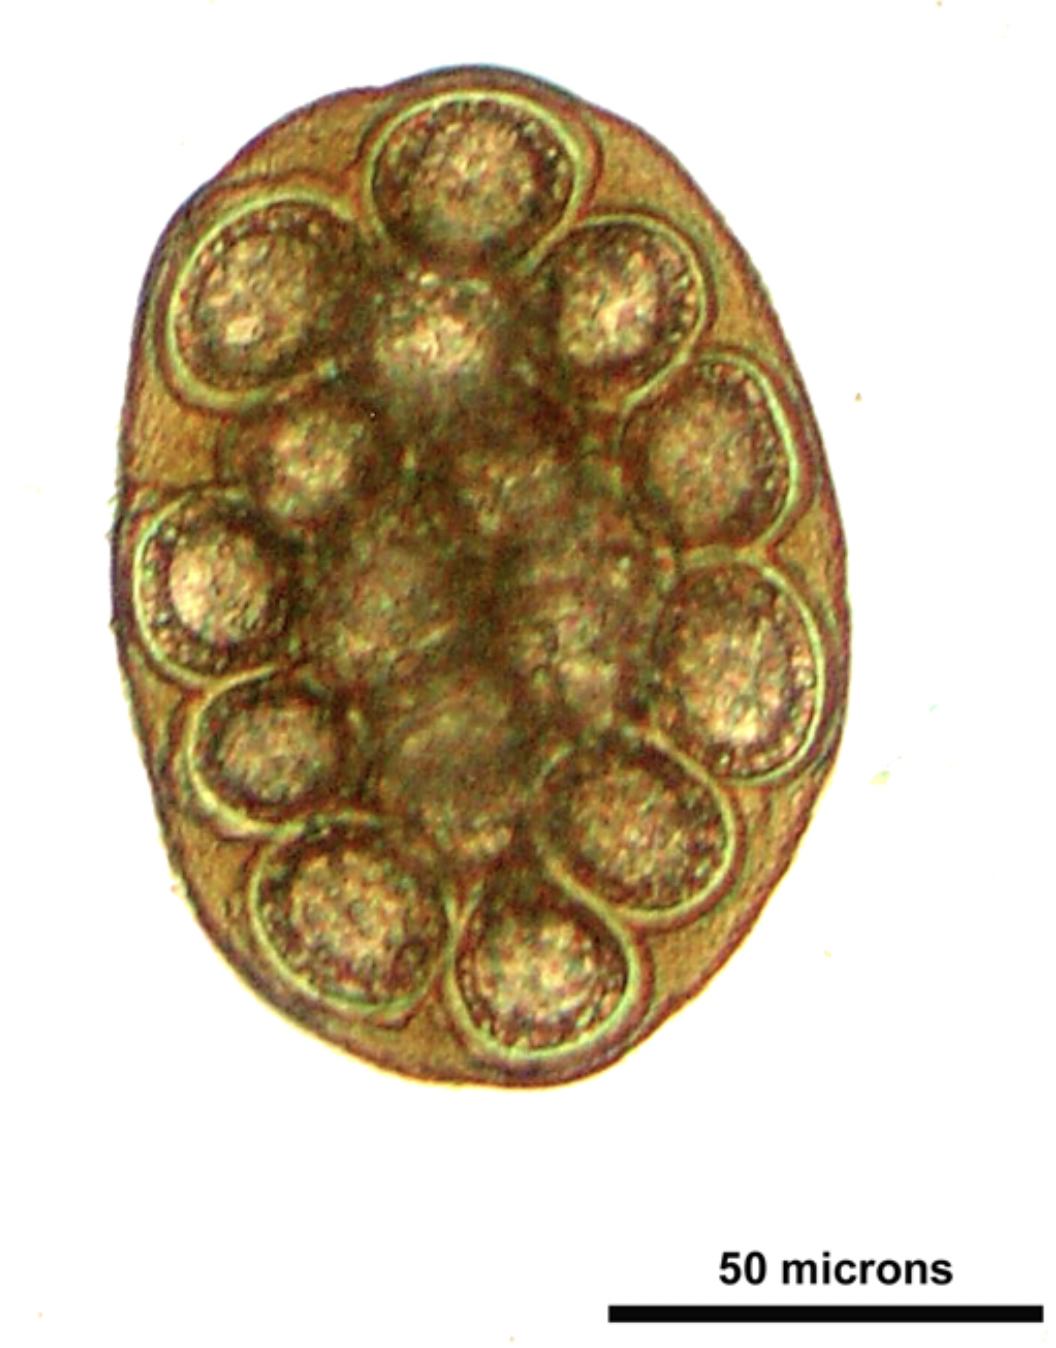

What is the infective stage of Eimeria parasites?

A

sporocyst

Q

this egg was found in the feces of a dog. which parasite is it from

Dipylidium caninum